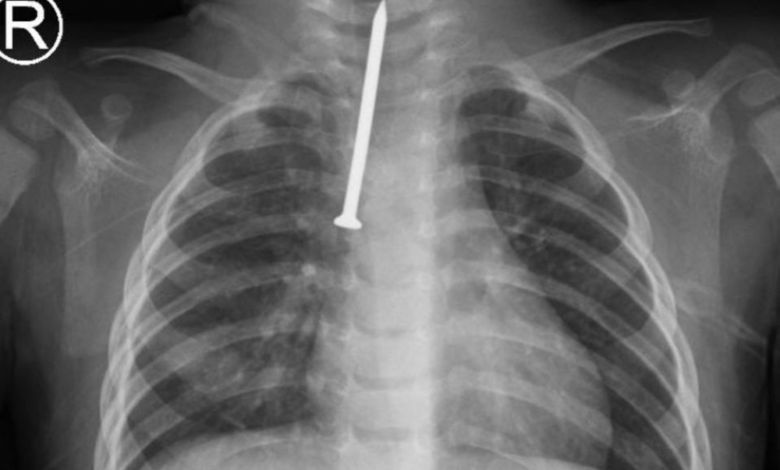

في تفاصيل هذا الحدث الطبي، استقبلت الطوارئ حالة حرجة جداً للرضيع الذي كان يعاني من اختناق وصعوبة حادة في التنفس نتيجة استنشاقه المفاجئ لجسم غريب. وبعد إجراء الفحوصات الإشعاعية اللازمة، تبين وجود مسمار معدني يبلغ طوله 5 سنتيمترات مستقر في المجرى الهوائي الرئيسي للطفل. على الفور، قرر الفريق الطبي بقيادة الدكتور محمد العصيمي، رئيس قسم جراحة الصدر ورئيس الفريق الجراحي، نقل الطفل بشكل عاجل إلى غرفة العمليات.

تم إجراء عملية تنظير صلب للقصبة الهوائية ومجرى التنفس، وهي تقنية طبية متقدمة تتطلب دقة متناهية لتجنب إحداث أي تمزق أو نزيف في الأنسجة الرقيقة للرضيع. وبفضل الله ثم بفضل كفاءة الفريق، تم استخراج المسمار بنجاح دون حدوث أي مضاعفات خطيرة، ليتجاوز الطفل مرحلة الخطر ويبدأ في التماثل للشفاء.